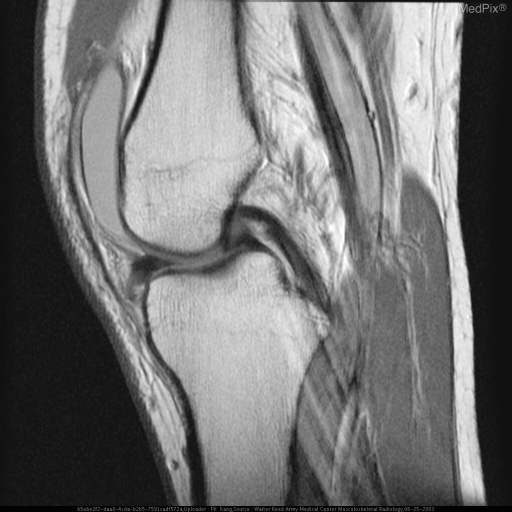

MRI sagittal showing normal meniscal anatomy

Sagittal MRI demonstrating the normal biconcave, low-signal meniscus positioned between femoral condyle and tibial plateau, with intact cruciate ligaments and infrapatellar fat pad.